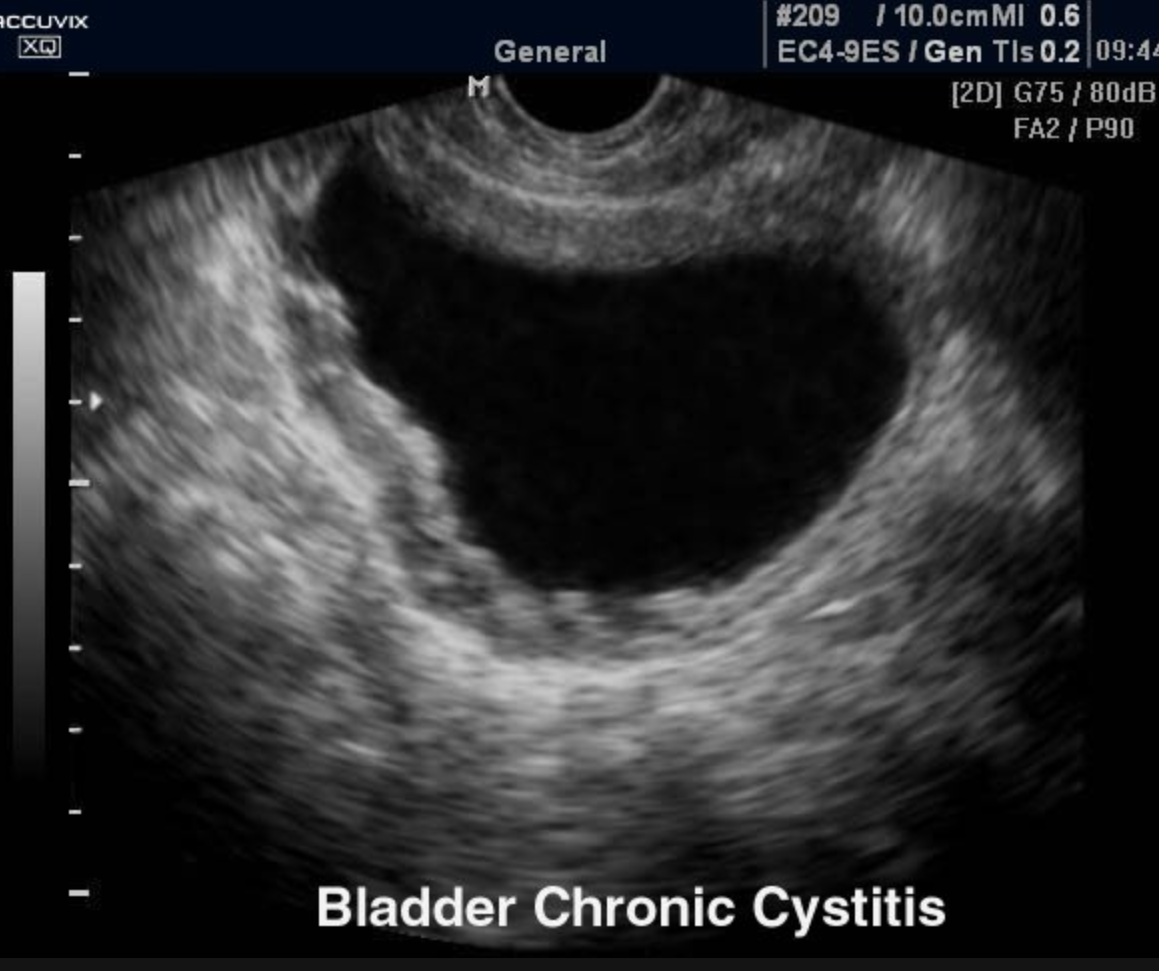

Define: inflammation of the bladder

cystitis

Is cystitis more common in men or women? Why?

women due to shorter urethra

Sono findings of cystitis (3)

- hypoechoic wall

- focally or diffusely thickened wall

- may contain echogenic material

Chronic cystitis can lead to ___

scarring and trabeculation of bladder wall